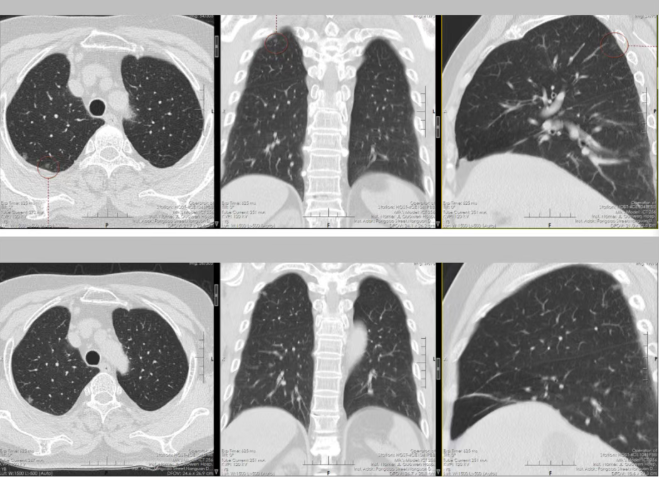

患者因常规体检发现右肺上叶多发结节前来我院就诊。完善胸部CT等相关检查后,影像显示其右肺上叶存在4枚大小、形态均有差异的结节,分布位置较为分散,且多枚结节具备恶性病变的高危特征。若按照传统诊疗模式,此类多发结节往往需分次手术切除,患者不仅要承受多次麻醉、多次手术切口的痛苦,还会面临住院周期延长、治疗费用增加的问题,同时反复手术会对肺功能造成累积性损伤,进一步加重身心负担。

接诊后,杨跃教授团队结合患者影像学资料、身体基础状况进行全面评估,精准研判每一枚结节的位置、潜在风险与病理性质。针对结节分布分散、恶性概率高的特点,团队最终制定出胸腔镜下精准定位+同步切除的个体化手术方案,计划通过单一微创切口,一次性完成4枚结节的完整切除,既实现病灶根治,又最大限度保留正常肺组织,助力患者术后快速康复。

手术当日,在麻醉科、手术室团队的紧密协作下,杨跃教授主刀,凭借娴熟的腔镜操作技术,在狭小的胸腔空间内精准定位每一枚结节,细致分离周围组织,避开血管与支气管,稳步完成4枚结节的切除。术中快速病理结果与术前评估高度一致,确认3枚结节为肺腺癌、1枚为癌前病变,手术切除范围精准、彻底,达到了根治性治疗。